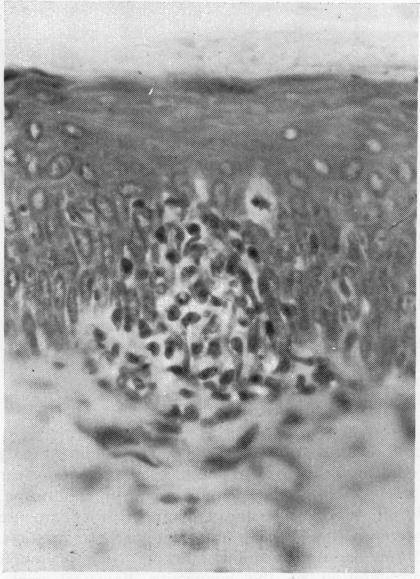

Workshop IV. Aetiopathogenetic factors in Reiter's syndrome. Adjuvant disease: pathology and immune reactivity.

Ann Rheum Dis. 1979;38 Suppl 1(Suppl 1):suppl 102-10. doi: 10.1136/ard.38.suppl_1.102.